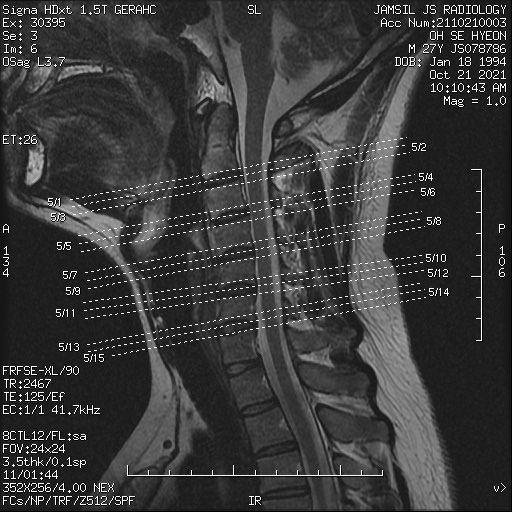

이 MRI 사진은 21년도 사고 당시 찍은 MRI 사진 입니다. 확인 부탁드립니다~

전체 mri를 다 봐여겠지만 보여주신 mri 컷에서는 의미있는 경추 디스크탈출이 보이지 않습니다.